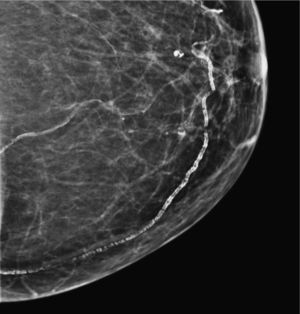

Mastitis de células plasmáticas (fig. 6). Es un proceso inflamatorio ductal y periductal. Las calcificaciones aparecen como resultado tardío de la enfermedad secretora. Suelen ser bilaterales, de forma lanceolada y bordes lisos, y se distribuyen orientadas hacia el pezón siguiendo la dirección de los conductos galactóforos1-3.